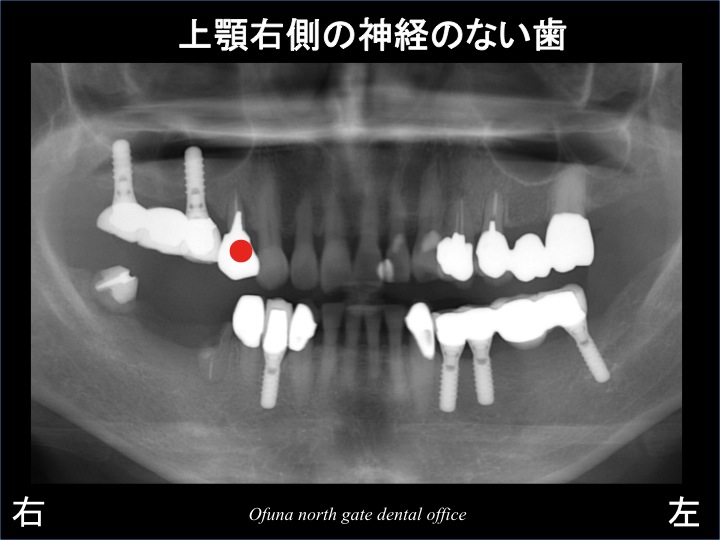

さてここで問題となったのが、神経のない歯です。

本日の本テーマでもある神経のない歯をどう考えるか? です。

以下のレントゲンは、神経がない歯を青丸で書いています。

神経のない歯は、どうしても将来性が低いのです。

そのため、上顎右側の●印などは、あらかじめ抜歯した方が良いのか?